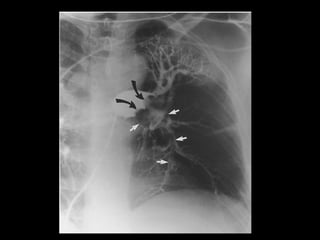

 Nas radiografias de tórax pode-se ver o sinal de

westermark .

CORCOVA DE HAMPTOM

São opacidades com base pleural e vértice voltado para o

hilo.

Ocorrem de 12 a 36 horas após o início dos sintomas e

indicam infarto pulmonar.

 Nas radiografiasde tórax pode-se ver o sinal de westermark .

CORCOVA DE HAMPTOM Sãoopacidades com base pleural e vértice voltado para o hilo. Ocorrem de 12 a 36 horas após o início dos sintomas e indicam infarto pulmonar.